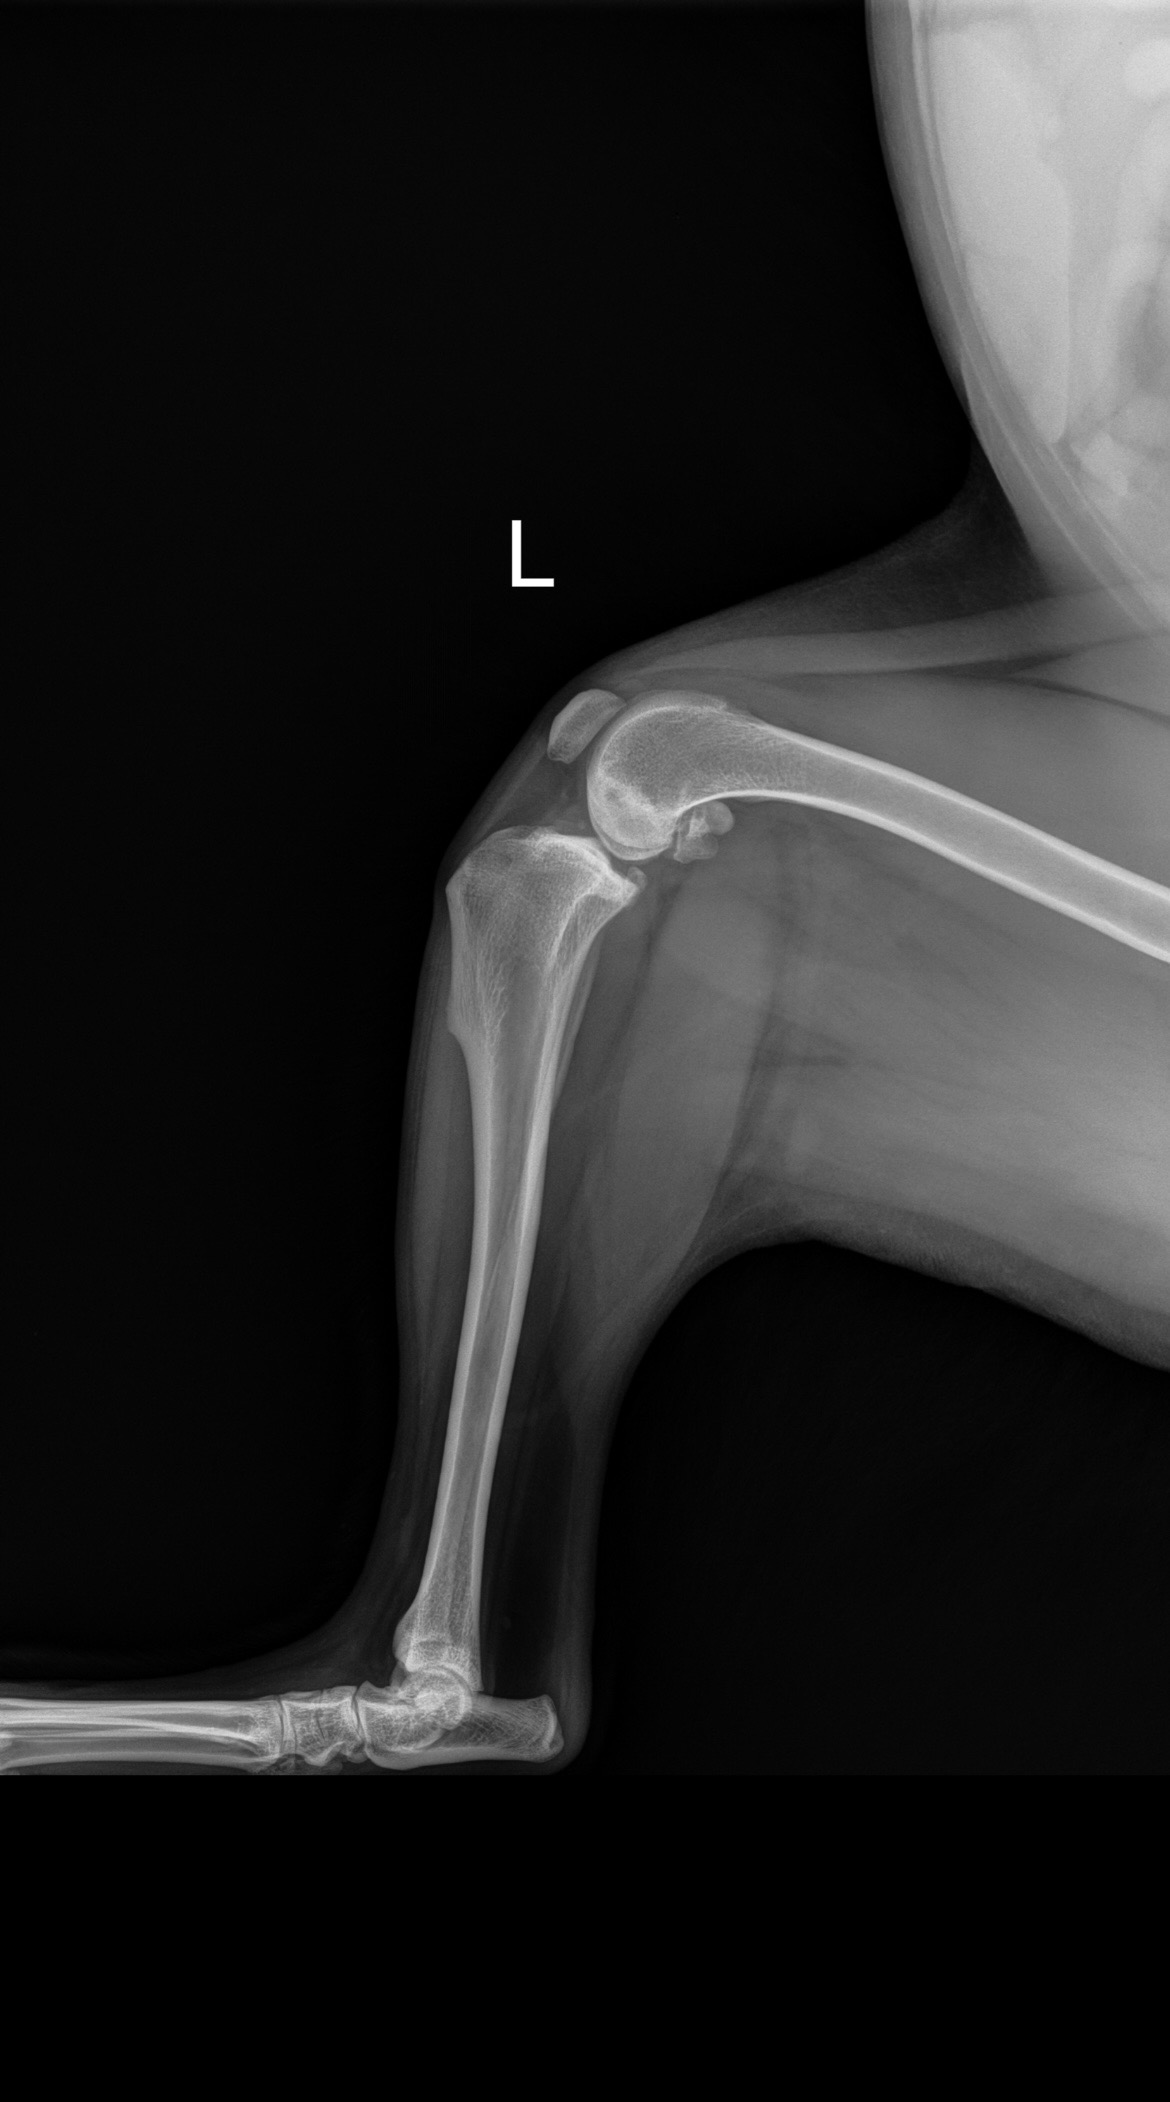

After a handful of primary vet visits, x-rays, consults with orthopedic surgeons and even second and third opinions later- we have confirmed a CCL tear (cranial cruciate ligament) in her left, hind leg. Reconstructive surgery is the only option.

This is similar to an ACL tear in humans.